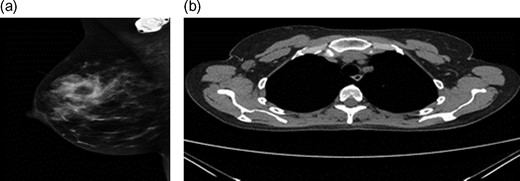

A 43-year-old female, 10 weeks postpartum, underwent colonoscopy for bleeding per rectum showing a bulky tumour (Fig. 1) in the rectum at 5 cm. Histologically poorly differentiated adenocarcinoma of the rectum (Fig. 2) T3N1Mo. Underwent laparoscopic loop ileostomy formation for impending bowel obstruction. Bloods showed Hemoglobin13.6 g/dL, Bilirubin 10umol/L, CEA 3.6 ng/mL. MRI pelvis (Fig. 3a and b) showed locally advanced annular neoplasm of mid and upper rectum. CT TAP (Fig. 4) reported no distant metastasis. She had neoadjuvant chemoradiothreapy with poor response. Post chemotherapy she noticed a lump in her right breast and axilla. Breast mammogram (Fig. 5a) showed 26 mm lesion in the right breast at 10 o'clock position and ultrasound showed 27 mm lesion in right axilla. Core biopsy (Fig. 6) reported signet ring morphology. The tumour stained positive with CK20, CDX-2 and CEA. There was no staining with CK7, ER, PR or Her-2. The rectal biopsy specimen, also analysed for KRAS status, was KRAS/NRAS/BRAF negative. She is being followed up by oncology with FOLFOX+Panitumumab.

(a) Mammogram post-neoadjuvant chemoradiothreapy showing right breast mass. (b) CT TAP pos-tneoadjuvant chemoradiothreapy showing enlarged right axillary lymph node.